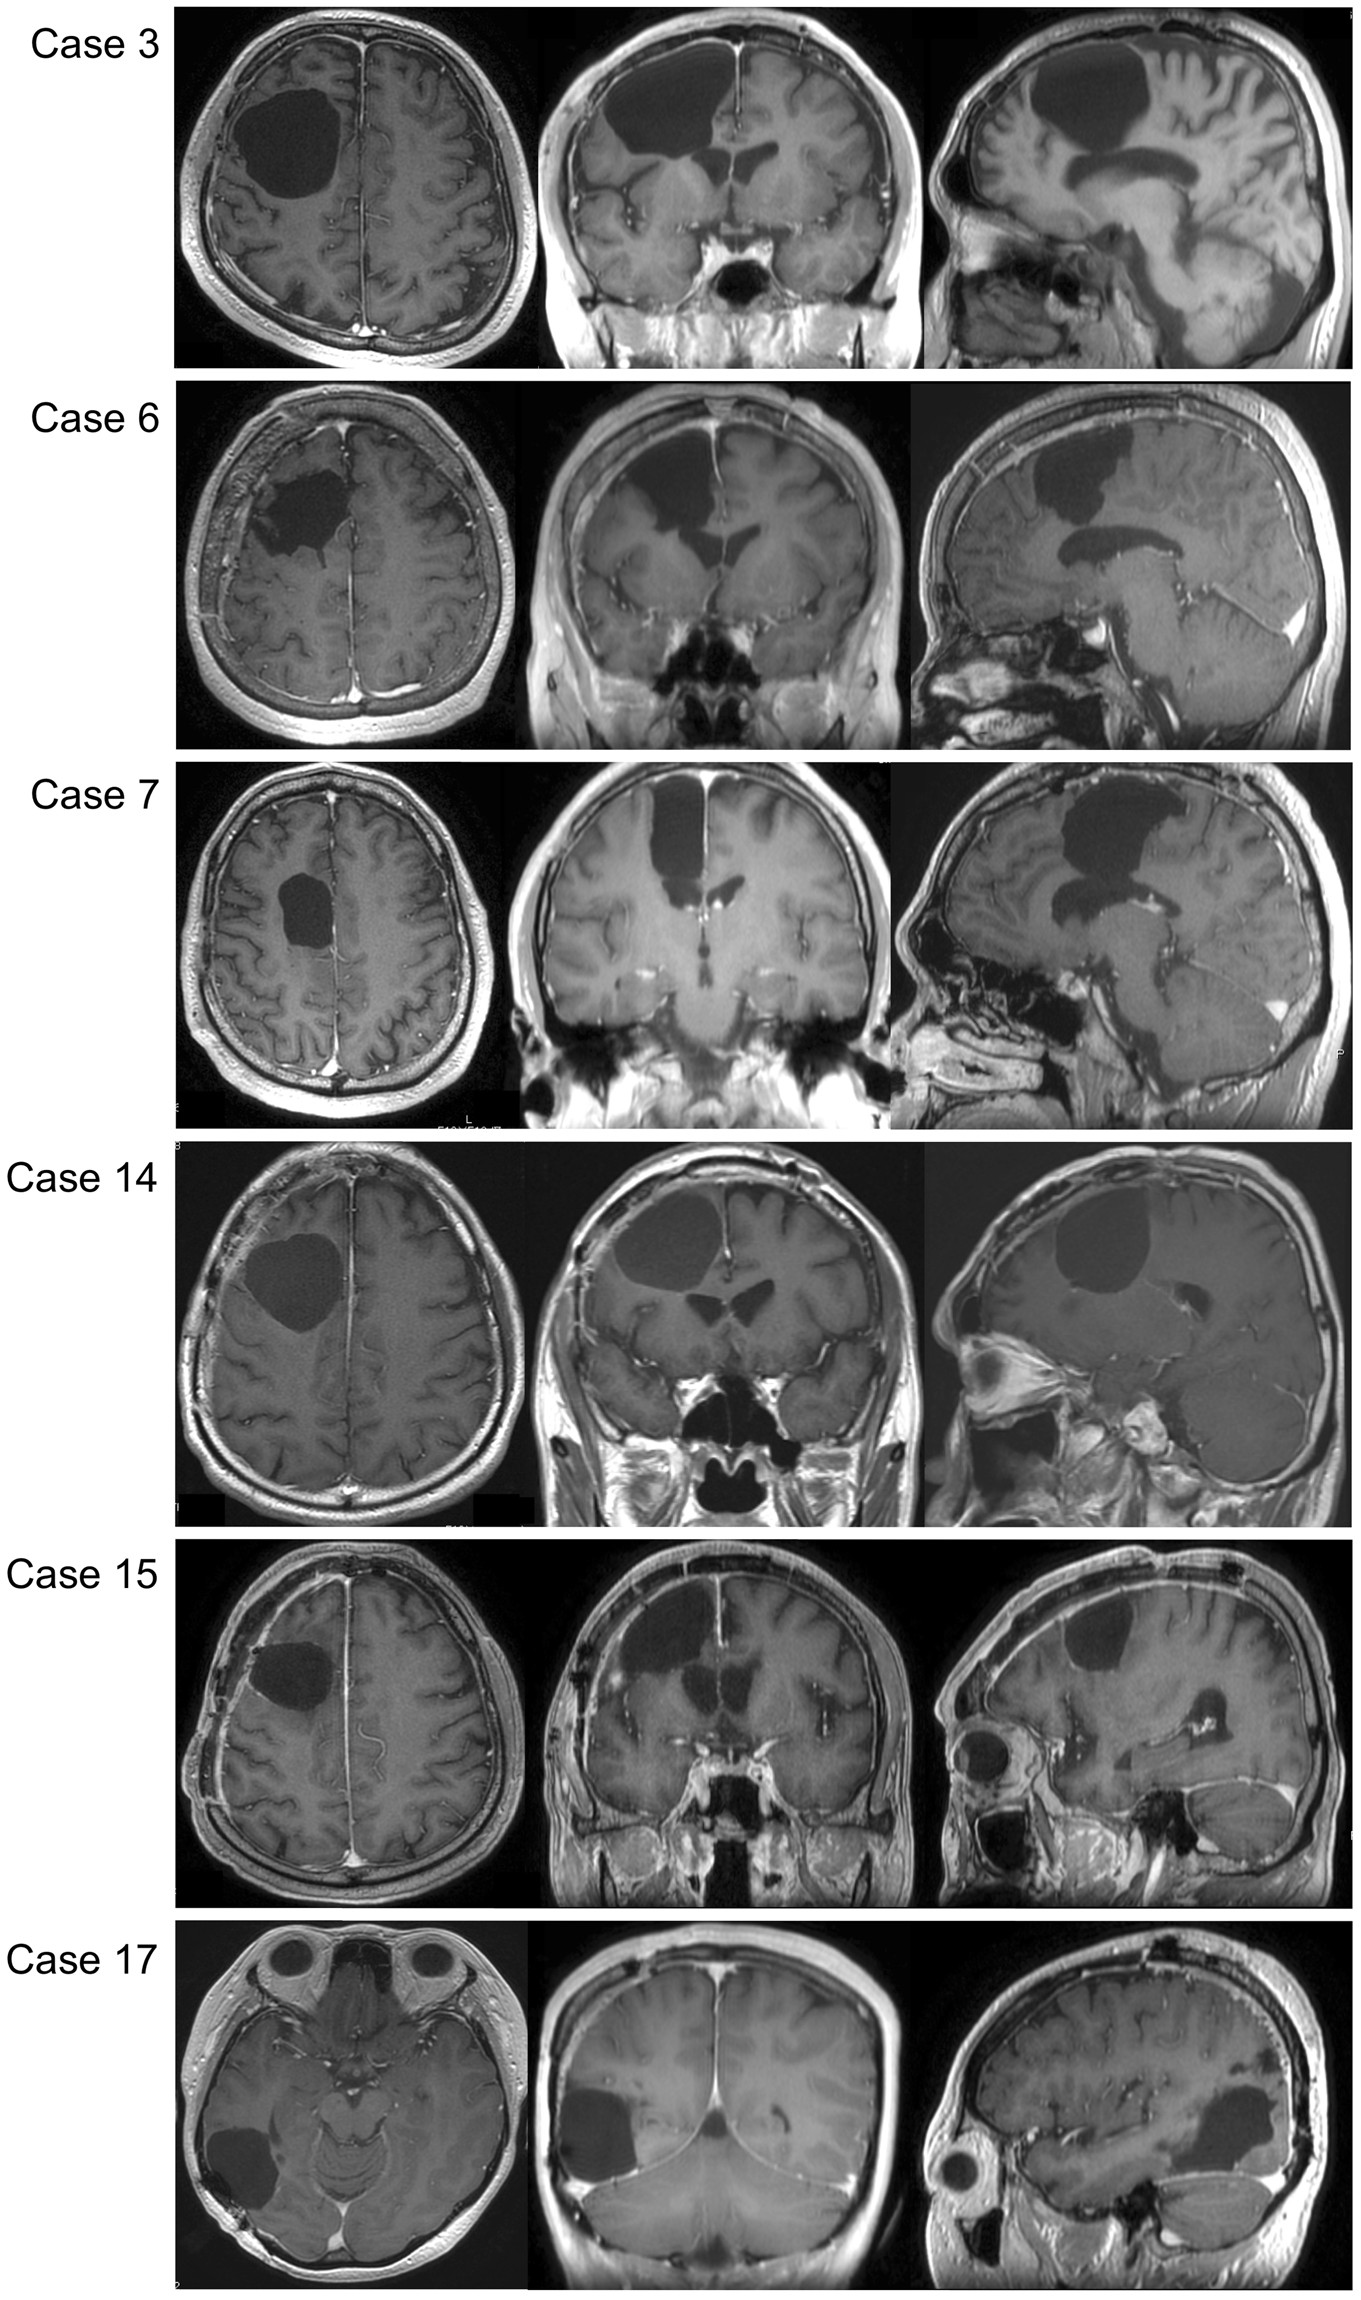

Figure 5

Postoperative MR images of patients whose visuospatial cognitive lasted ≥3 months. In the left, middle and right columns, T1 weighted MR images of axial, coronal, and sagittal slices, respectively, are shown for each patient. Resection cavities are in the middle frontal gyrus and/or superior frontal gyrus including the medial region in patients with frontal lesion.